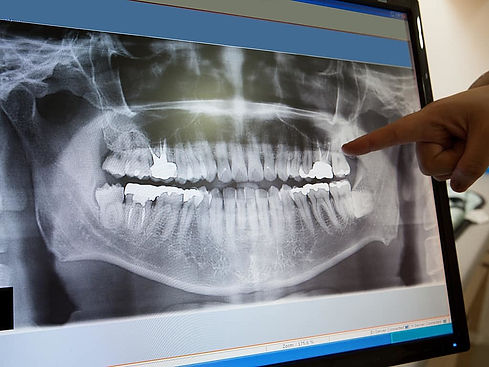

Radiologie dentaire

Il s'agit d'un outil de diagnostic précieux qui permet de déceler de façon précoce une pathologie dentaire et d’anticiper avant même que celle-ci deviennent douloureuse.

La panoramique dentaire permet également d'obtenir un historique sur les différents soins apportés.